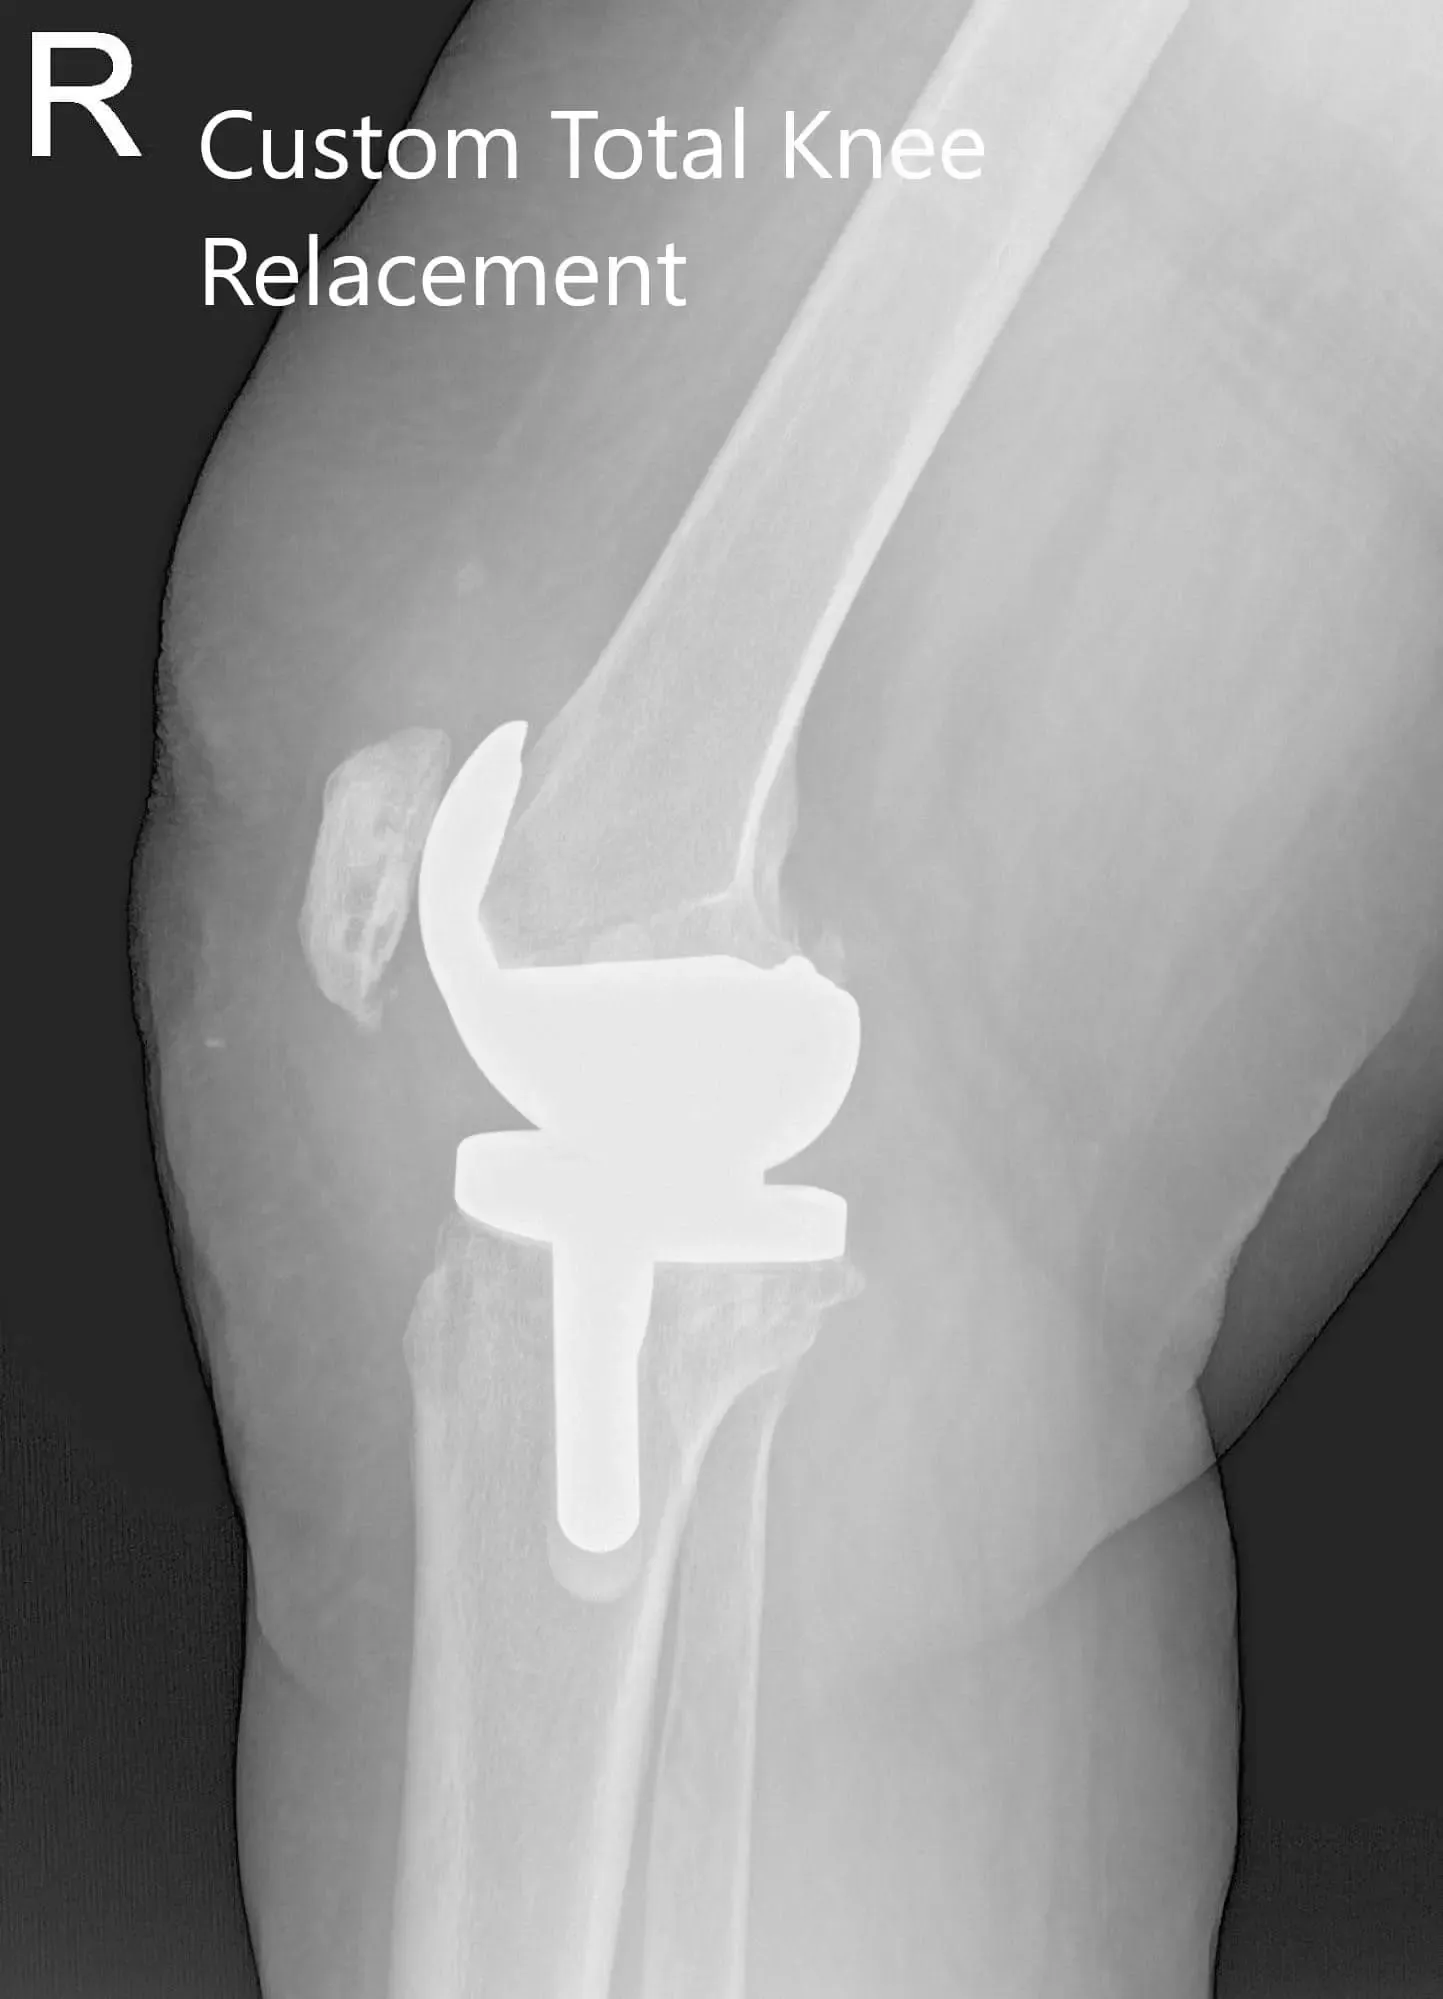

OPERATION: Right total knee arthroplasty using custom femoral component with a custom tibial tray with polyethylene 6 mm with patella 32 mm x 6mm.

Postoperative X-ray of the right knee showing AP and lateral views